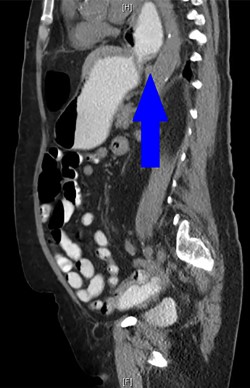

During the hospitalization, initial cardiac workup with 12-lead electrocardiogram and serial troponins was negative. The patient’s oncologic medications were held without improvement of the pain as well as to prevent leukopenia and neutropenia, if surgery was indicated. Palliative care was unable to achieve adequate pain control with oral and IV medications, and the patient did not want to pursue hospice care. Surgical consultation was obtained, and further evaluation with a CT scan of the chest, abdomen and pelvis with oral and IV contrast demonstrated an anteromedial diaphragmatic defect through which a prominent amount of mesenteric fat and a portion of the colon herniated representing a Morgagni hernia (Figs. 1–4). An increase in the size of the previously known PEH as well as the Morgagni hernia was noted. Due to continued chest pain unrelieved by opioids, a joint decision was made between surgeon, oncologist and the patient to proceed with surgery. She underwent successful robotic laparoscopic repair of the Morgagni hernia and PEH with dulex mesh for reinforcement. Her chest pain subsequently resolved. The patient gradually tolerated oral feeds and was eventually discharged in stable condition.

A sagittal view from the 2017 CT chest, abdomen and pelvis with IV and PO contrast demonstrates the Morgagni hernia with fat sweeping up through the diaphragmatic defect (red arrow) and a retrocardiac paraesophageal hernia (blue arrow).